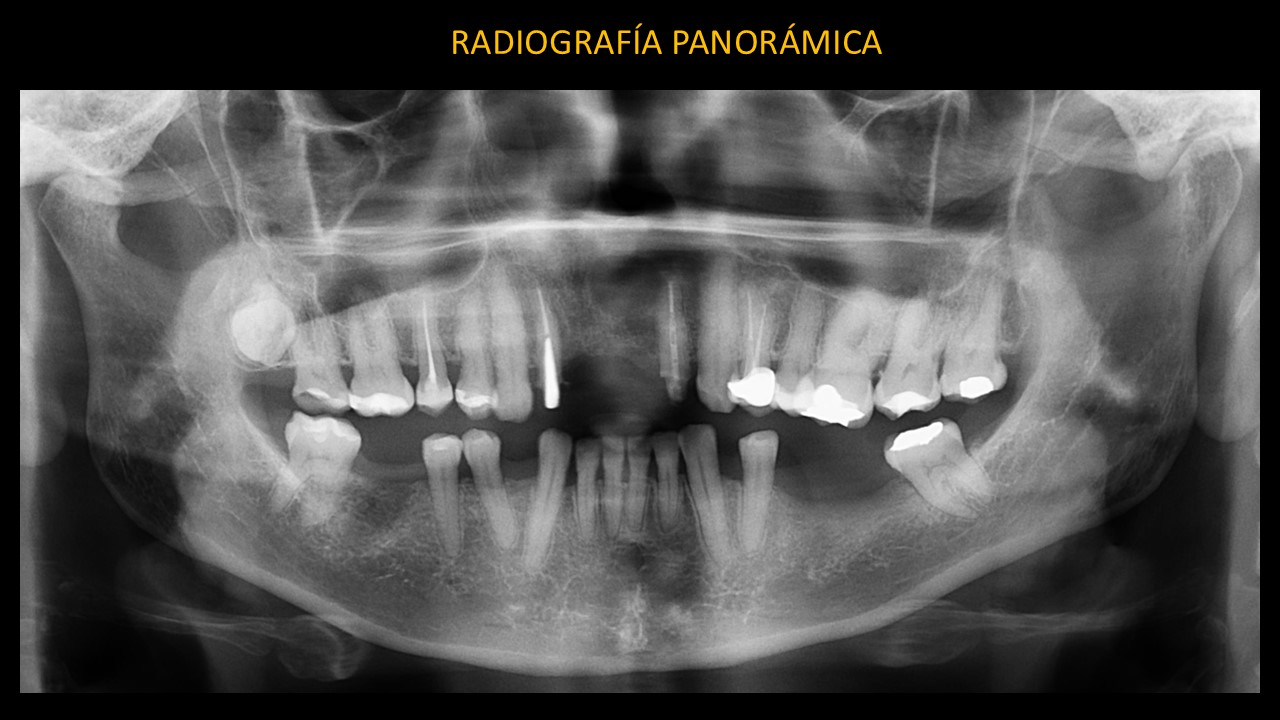

En la radiografía panorámica (Figura 1) se evidencia una imagen radiolúcida en la línea media del maxilar superior, de límites definidos, bordes corticalizados y forma redondeada.